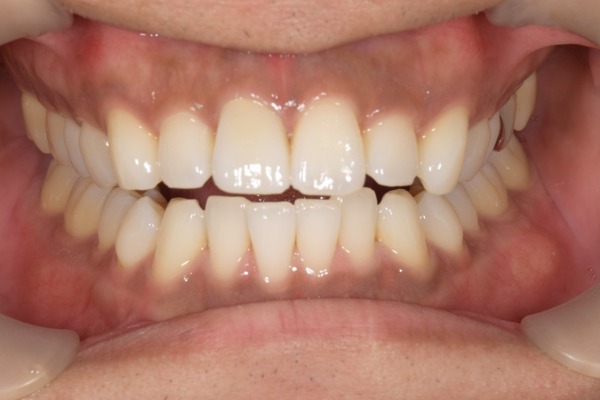

治療後の様子

患者様はジルコニアと歯の色調が自然に見えることや噛み合わせが改善されたことにご満足されました。